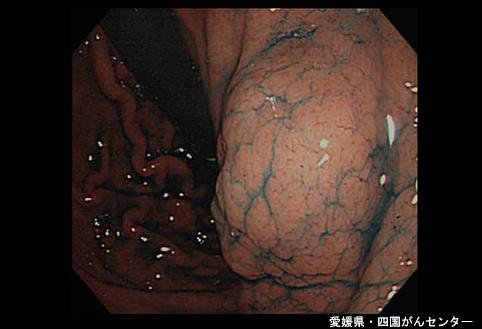

A case of ectopic pancreas in the stomach.

[ Image ID:4971 ]

Tumor-like lesions/ectopic mucosa

Stomach/Angle

Endoscopy

40 -